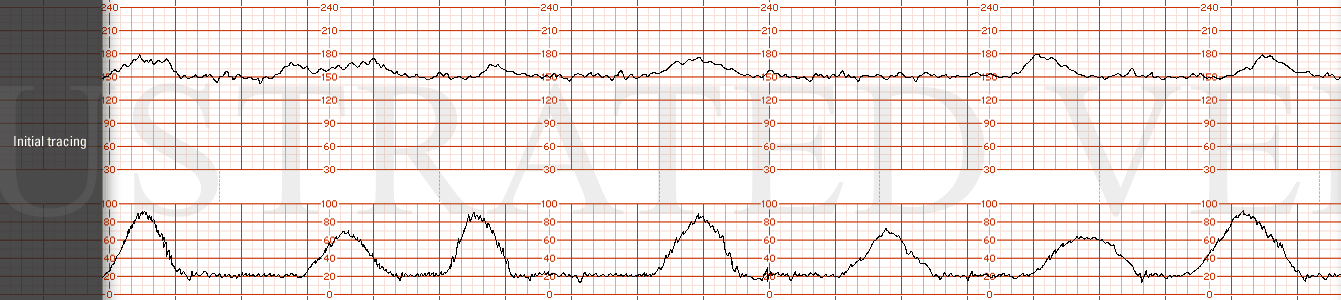

STRIP 22

1. The fhrt is as follows: (baseline hr 150 bpm, normal variability, one acceleration. 1 classic late deceleration is seen in a series of 5 contractions occurring over a 10 minute window. (the late decelerations are too deep (some are nadiring at 50-60 bpm below baseline. Normal lates are more subtle usually 10-30 bpm at most below baseline)